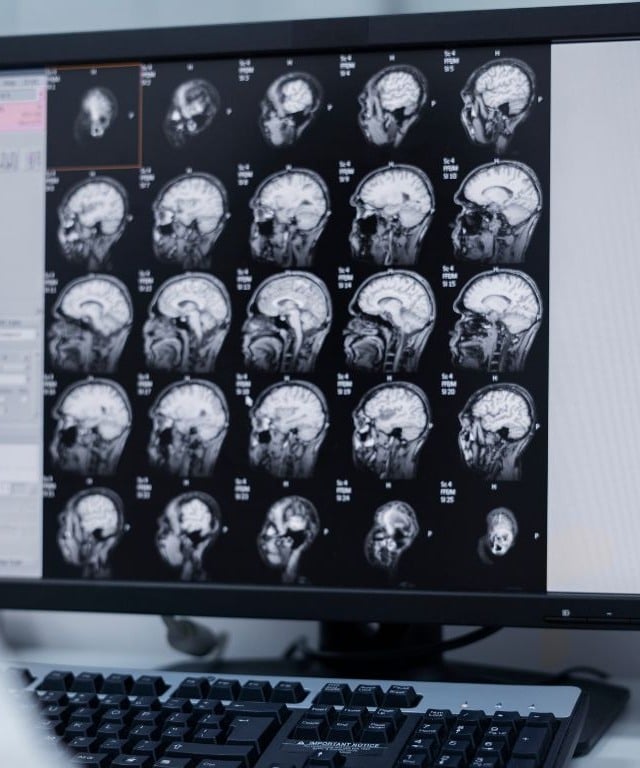

Menos de 1 em cada 3 países tem preparo para enfrentar o crescimento de doenças neurológicas, de acordo com o relatório Global status report on neurology, divulgado pela Organização Mundial da Saúde (OMS) nesta terça-feira, 14. As doenças do tipo são responsáveis por mais de 11 milhões de mortes por ano e afetam mais de 40% da população mundial.

Segundo a OMS, as 10 principais condições neurológicas que mais têm contribuído para mortes e incapacidades são: acidente vascular cerebral (AVC), encefalopatia neonatal, enxaqueca, doença de Alzheimer e outras demências, neuropatia diabética, meningite, epilepsia idiopática, complicações neurológicas associadas ao parto prematuro, transtornos do espectro autista e cânceres do sistema nervoso.

Nós estamos vendo uma epidemia neurológica. Muitas das principais doenças e condições patológicas são associadas a questões neurológicas, desde as coisas mais simples, como dores de cabeça e tonturas, até doenças cerebrovasculares, como AVCs, e doenças demenciais, como Alzheimer.

Diogo Haddad, neurologista do Hospital Nove de Julho e coordenador do núcleo de Memória do laboratório Alta Diagnósticos